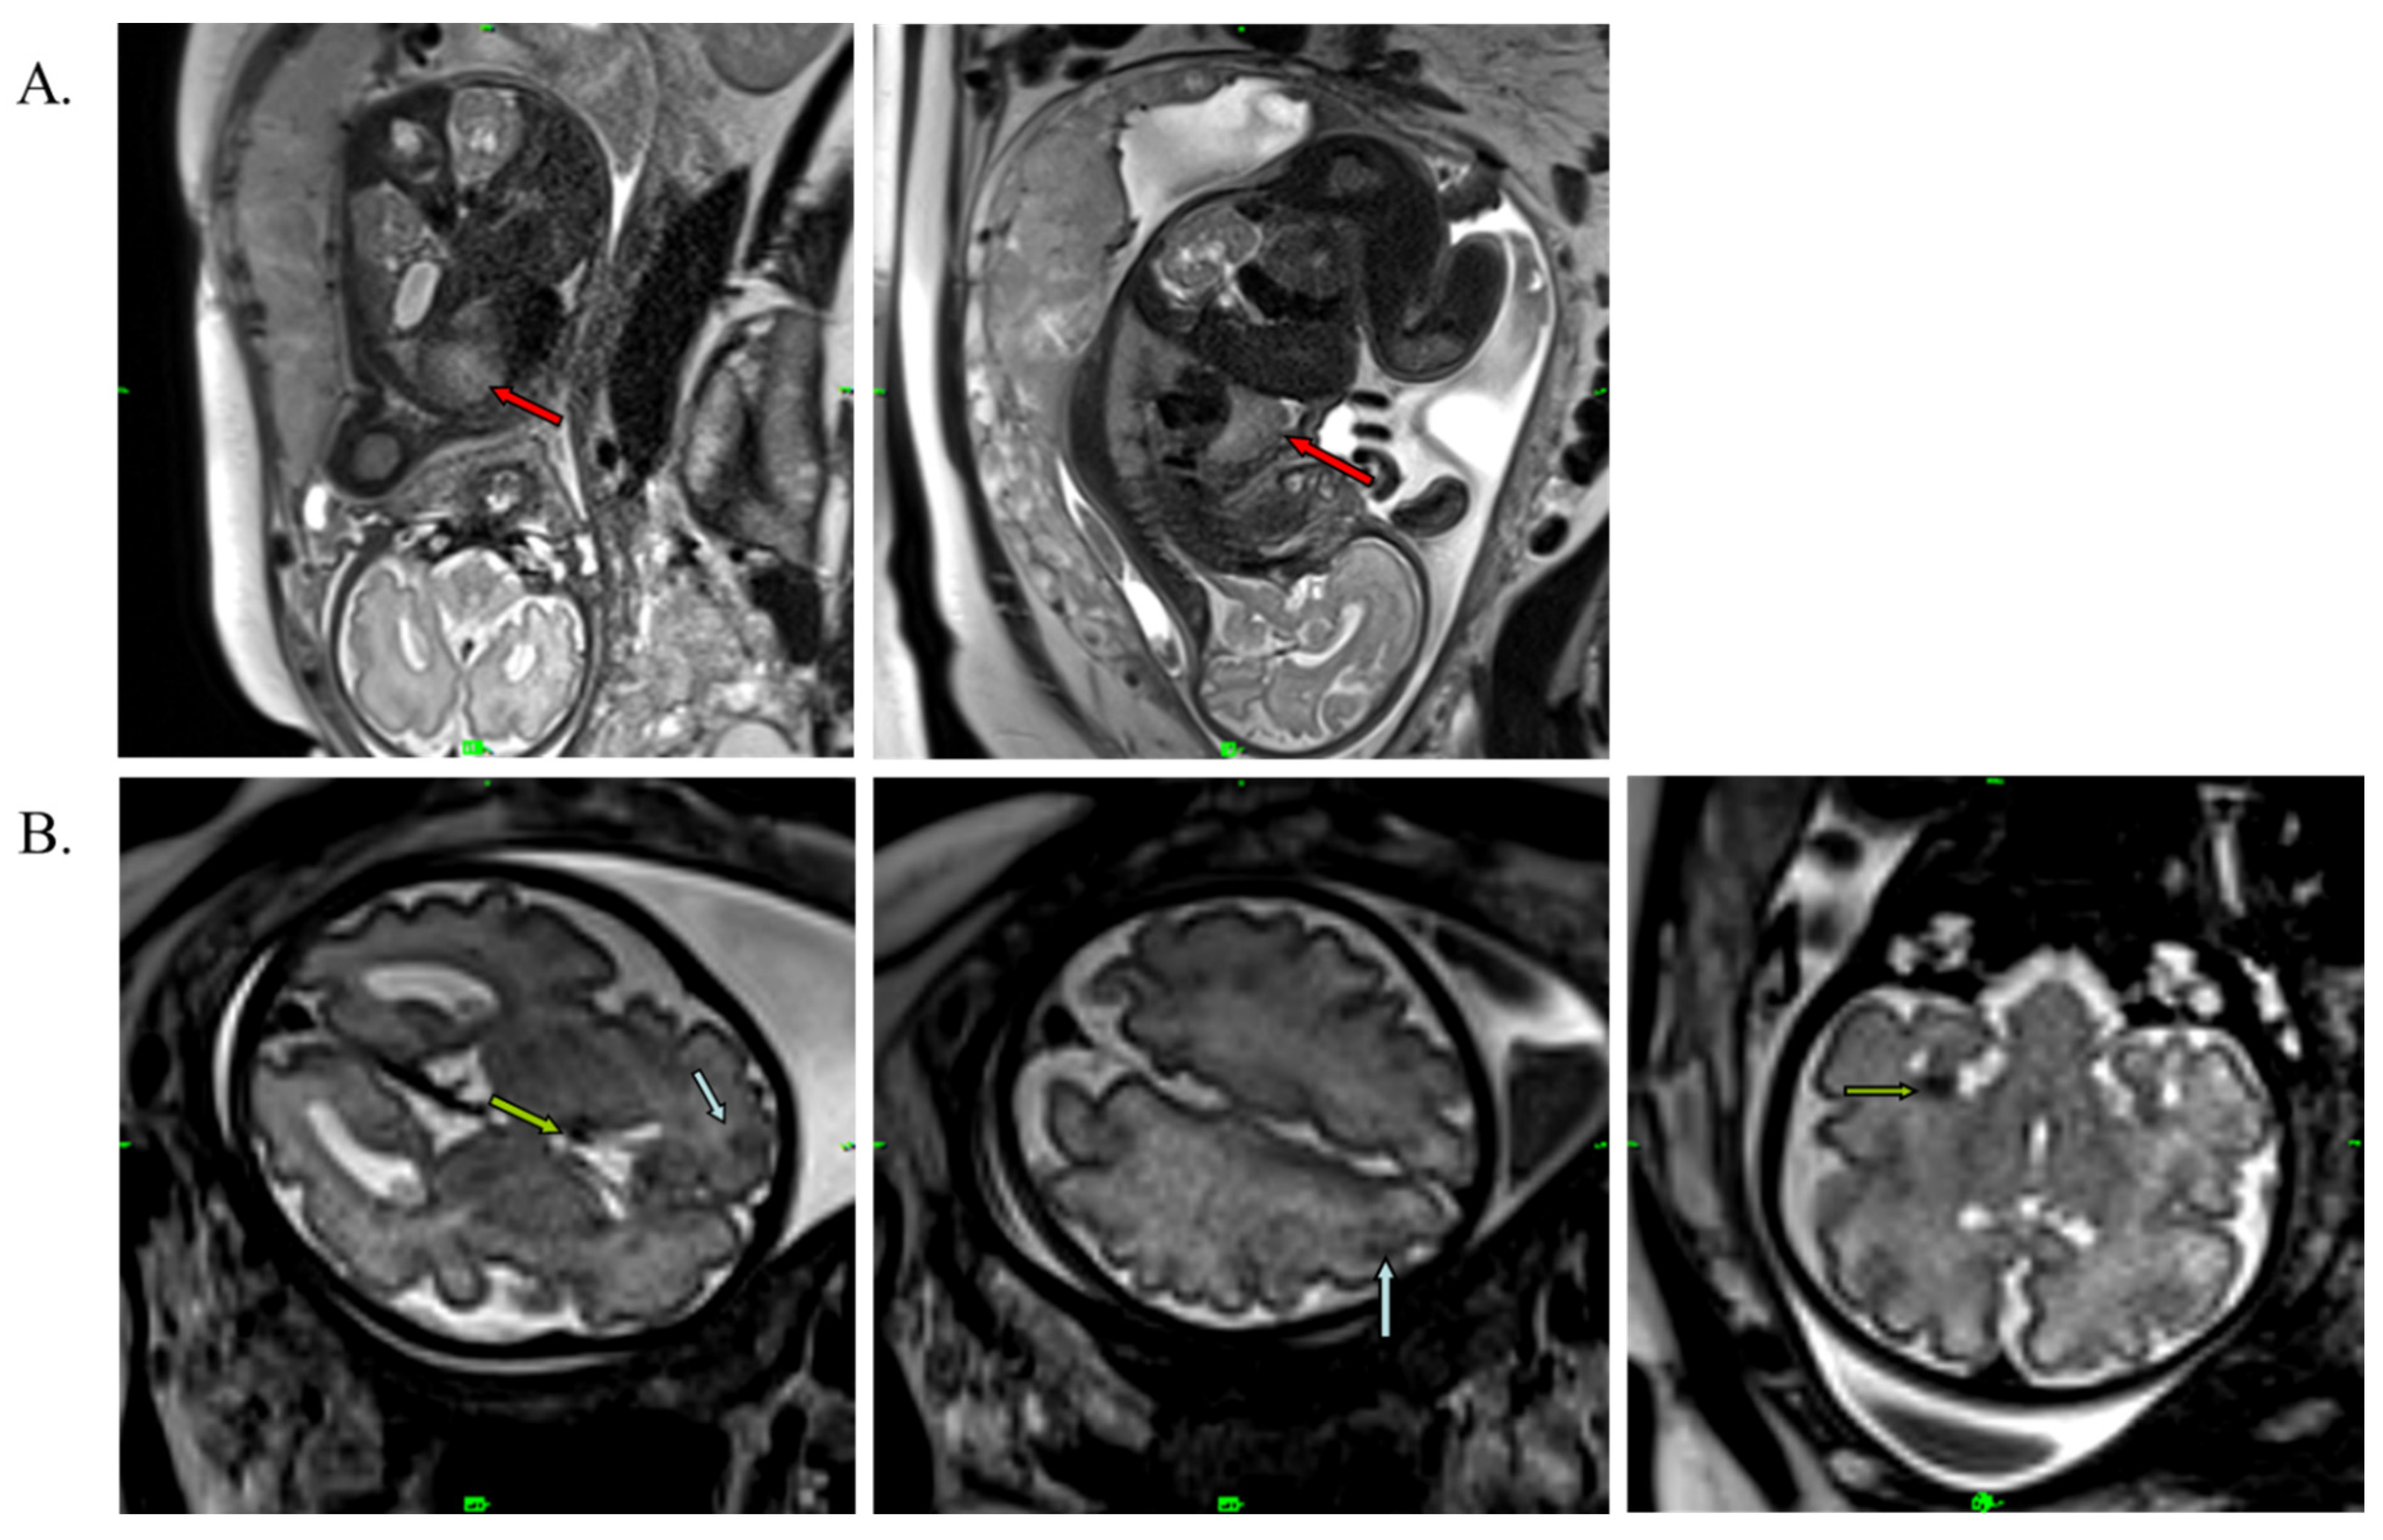

A 34-year-old pregnant woman was referred for examination at the Department of Obstetrics and Gynecology in her 30th week of gestation. The pregnancy was uncomplicated, and fetal parameters, including the abdominal circumference, femur length, and biparietal diameter, were consistent with the gestation age. An abnormal cardiac ultrasound scan of the fetus initiated a fetal echocardiography with a GE Voluson E8 high-end ultrasound system (GE Healthcare, Chicago, IL, USA). Left ventricular expansion was interpreted as a rhabdomyoma (31 × 32 × 33 mm), and some smaller tumors (multiplex tumors) were detected (Figure 1A). The fetal cardiac rhythm was a sinus without arrhythmia. In addition, echo-dense formations (cortical tubers and subependymal nodules) were also described in the brain tissue using fetal magnetic resonance imaging (FMRI), including T2-weighted imaging obtained using HASTE IRM (Siemens Healthcare GmbH, Erlangen, Germany) (Figure 1B).

Figure 1.

T2-weighted MRI image of the fetus at the 30th week of gestation. (A) Red arrows show cardiac rhabdomyoma (31 × 32 × 33 mm). (B) Blue arrows show cortical tubers, and green arrows represent subependymal nodules in the brain.